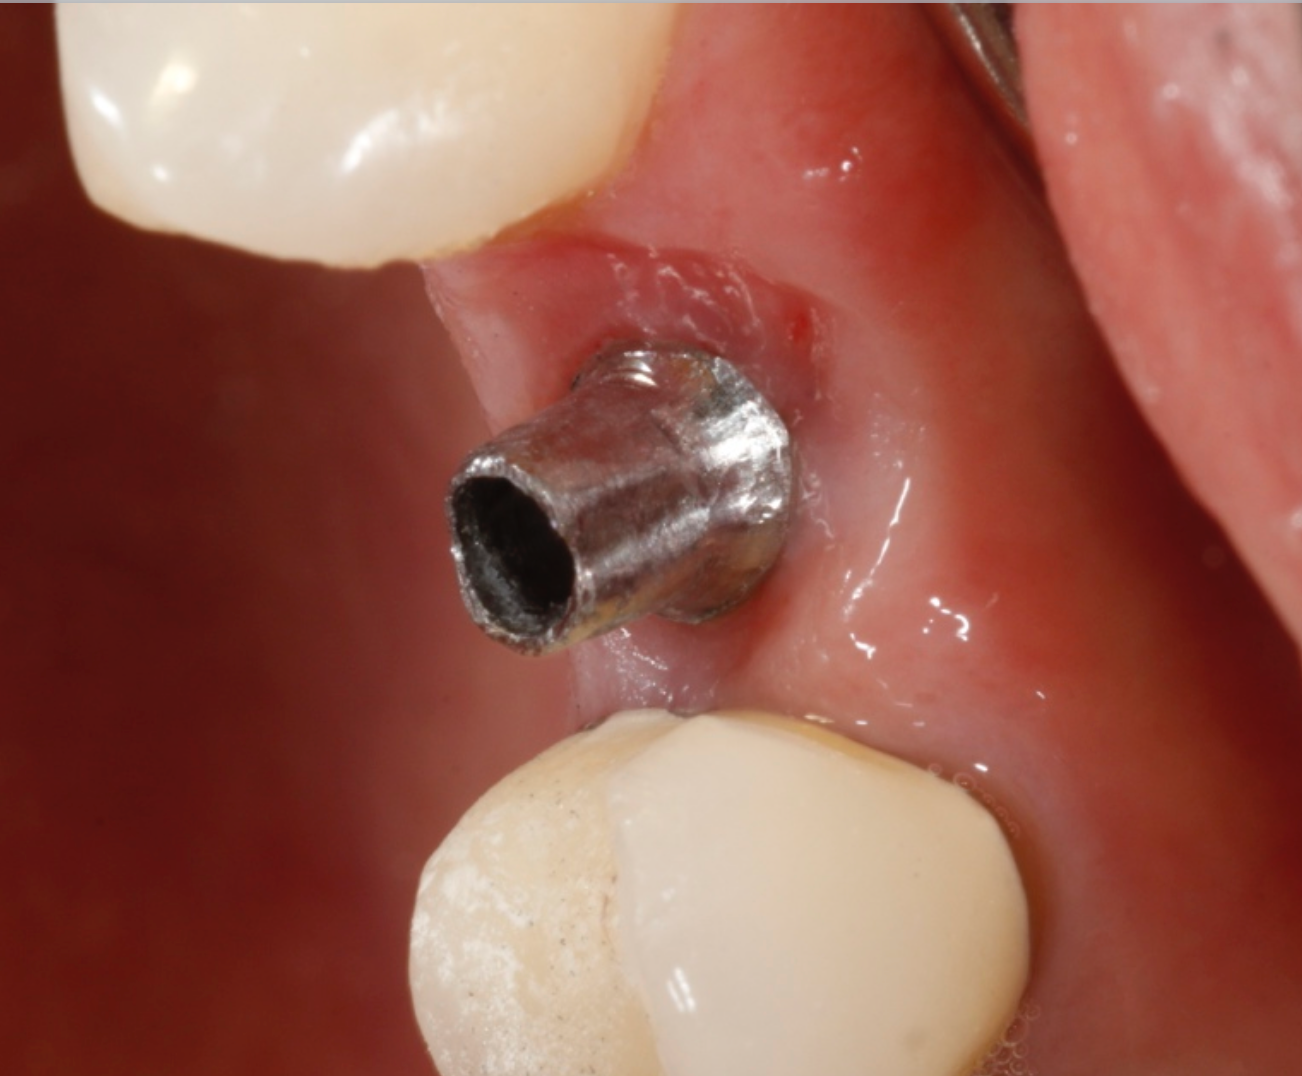

The implant in the tooth #12 area on the 50-year-old female patient is ready for restoration. In this instance, a stock abutment was selected and prepared extraorally. The abutment was placed to 25 ncm torque.

The PlanmecaFit with the Planmeca Emerald™ scanner (Figs. 7-8) was used to take a set of digital impressions, and the restoration was milled in the PlanMill® 40 S using an Ivoclar Vivadent IPS e.max block shade A1.